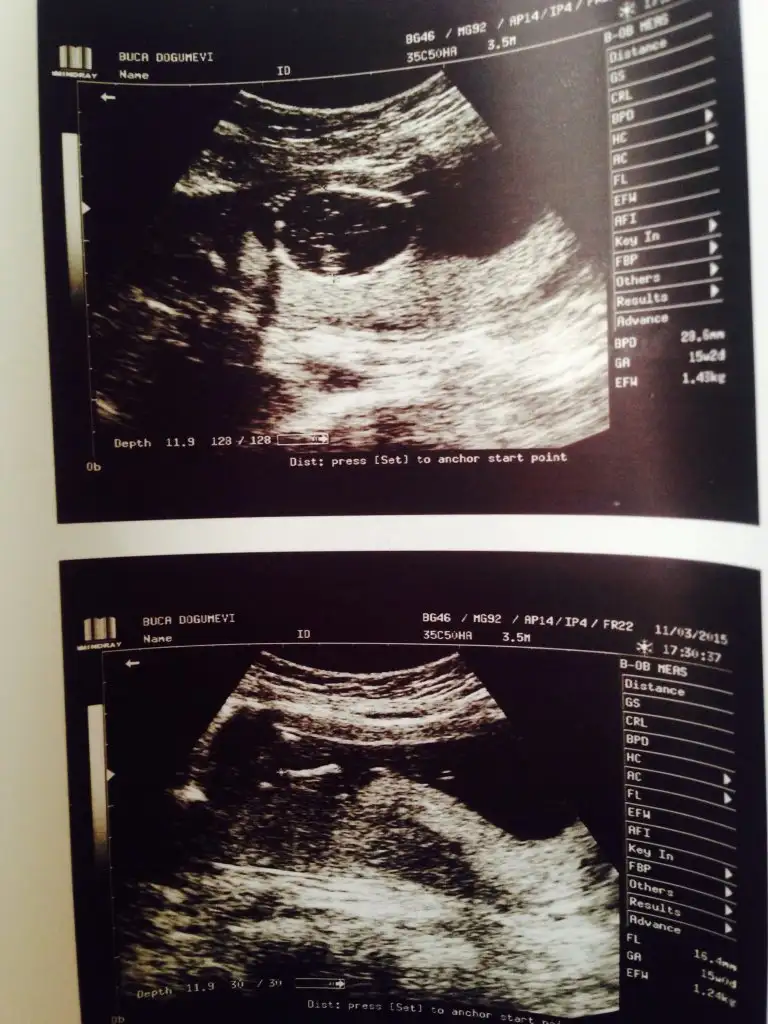

dr soylemeden siz gorun genital nub teorisi ( bebegin cinsiyeti)

kızlar benim bebeğimede bakar mısınız yorum yağar mısınız

kızlar 9+1 dedi cinsiyet tahmin edebilir misiniz